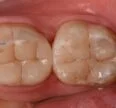

Problem: this 14 year old girl with a history of rampant decay was referred to me for esthetic and functional improvement from a specialist. Many fillings were leaking with extensive caries underlying.

Addendum: The patient also desired whiter teeth. Of note, the only “virgin” tooth was her upper right front tooth (upper left when you are looking at her from the front in this view) – we actually did not touch this tooth at all but decided to see if we could match the others to it.